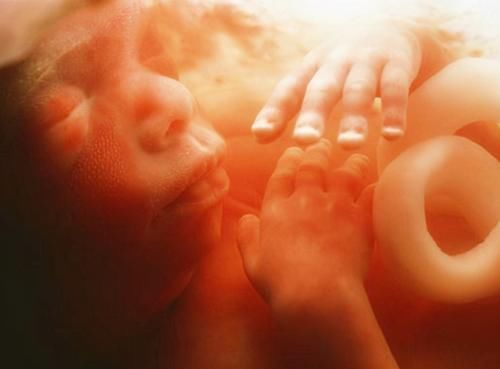

2、胎儿不配合

宝宝又不是成年人,能够配合医生摆出最好看的拍照pose,事实上他压根就不知道你们在干嘛,你们这边在拍照,他照样干自己的事情。

有可能用小手捂脸,把手举过头顶,甚至有可能故意“做鬼脸”,这些都会影响最终的图片效果。

如果想要拍出好看的照片,除非那个时候宝宝正处于精致状态,而是四肢都是放松的,没有遮挡住自己的小脸。